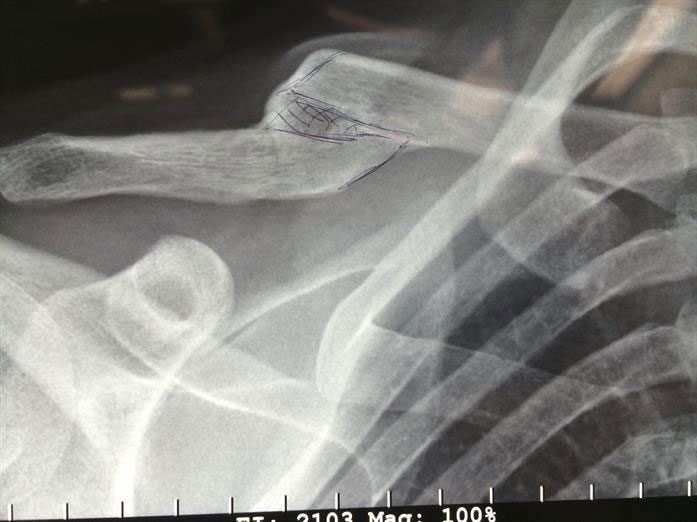

An x-ray example of a poorly healed old clavicle fracture.

The individual will attend an initial appointment. I’ll perform a physical examination, where I’ll take measurements, look for an obvious bump and assess the shoulder’s position. An X-ray or a CT scan might also be needed. I’ll also review the their overall health and medical history to ensure there are no risk factors that might prevent the bone from healing.